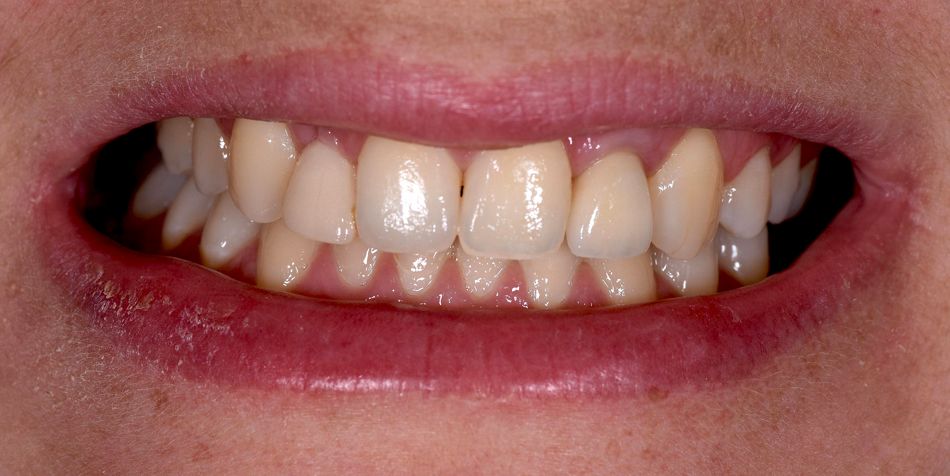

A healthy 26-year-old female patient with lateral incisor agenesis wanted a fixed solution for the missing tooth. She had good oral hygiene and was wearing an acrylic Maryland bridge as a provisional restoration. (Fig. 1-2)

After an esthetic evaluation, it was concluded that she had a medium smile line (Fig. 3), rotation of tooth 13, an overjet of 4 mm, and generalized gingival recession that was more pronounced in the canine area. Treating this gingival recession was not an immediate priority, although it was in the patient’s future interests.